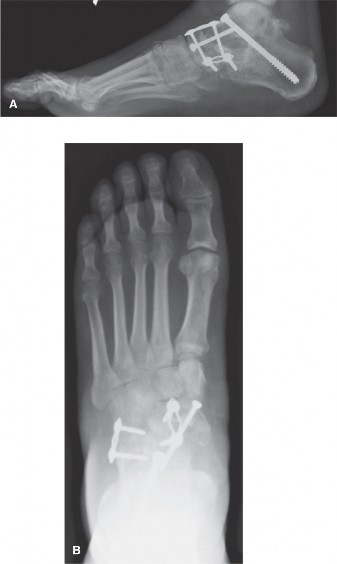

- Medializing Calcaneal Osteotomy:

- A lateral approach to the calcaneus is utilized (distinct from the medial incision for the PTT).

- A laterally based wedge or a simple transverse osteotomy is performed through the posterior tuberosity of the calcaneus, perpendicular to the long axis of the bone.

- The distal fragment is then translated medially, correcting the hindfoot valgus.

- Fixation is achieved with two or more cancellous screws.